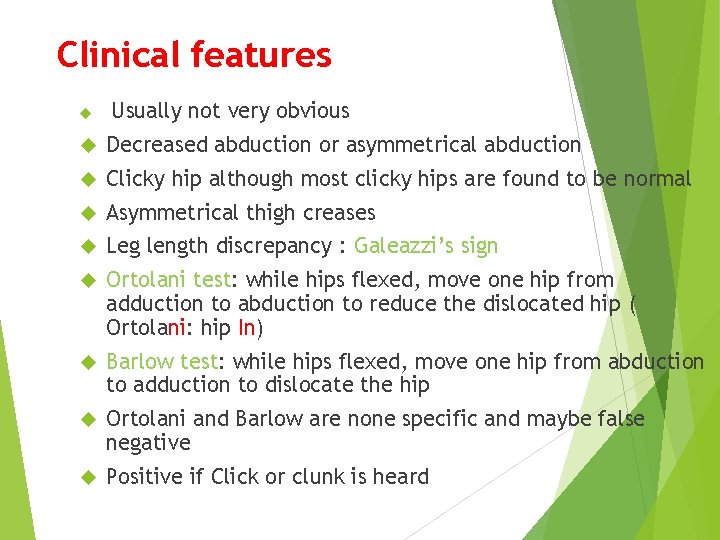

Clinical features Usually not very obvious Decreased abduction or asymmetrical abduction Clicky hip although most clicky hips are found to be normal Asymmetrical thigh creases Leg length discrepancy : Galeazzi’s sign Ortolani test: while hips flexed, move one hip from adduction to abduction to reduce the dislocated hip ( Ortolani: hip In) Barlow test: while hips flexed, move one hip from abduction to adduction to dislocate the hip Ortolani and Barlow are none specific and maybe false negative Positive if Click or clunk is heard